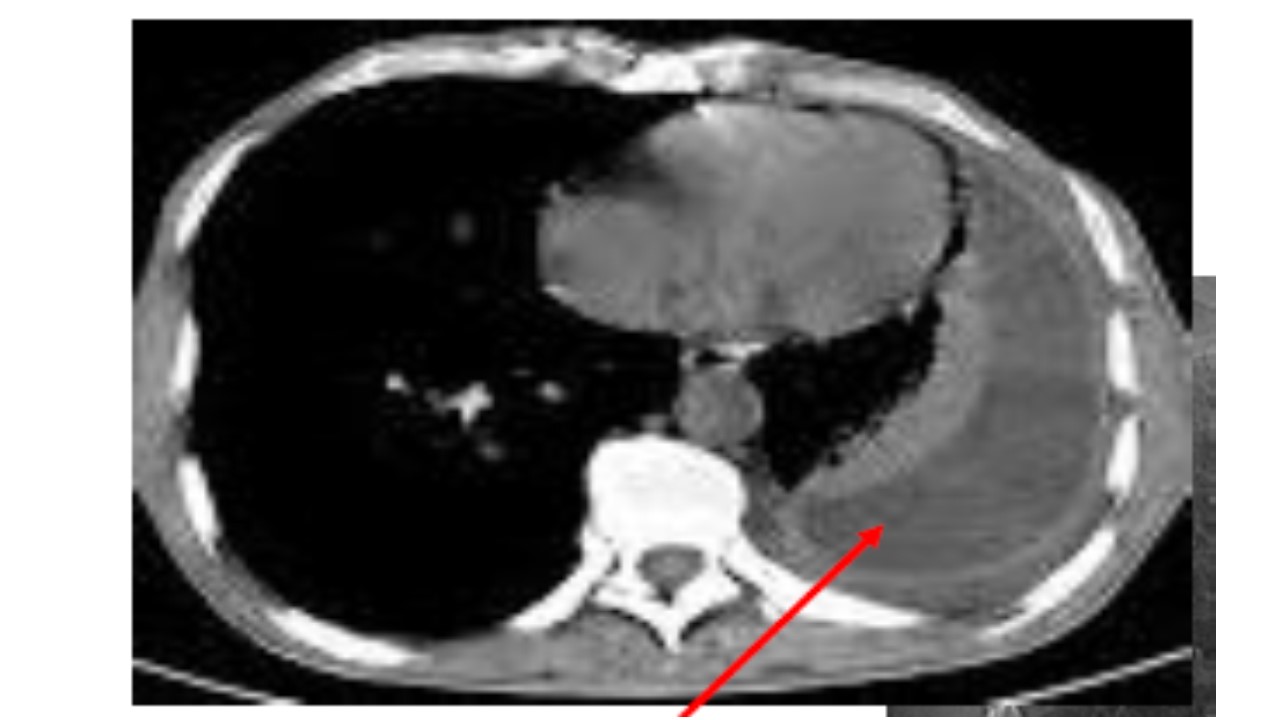

SINDROME HEPATOPULMONAR (SUGERIDA POR IMAGEM): BELO CASO

Imagem 2